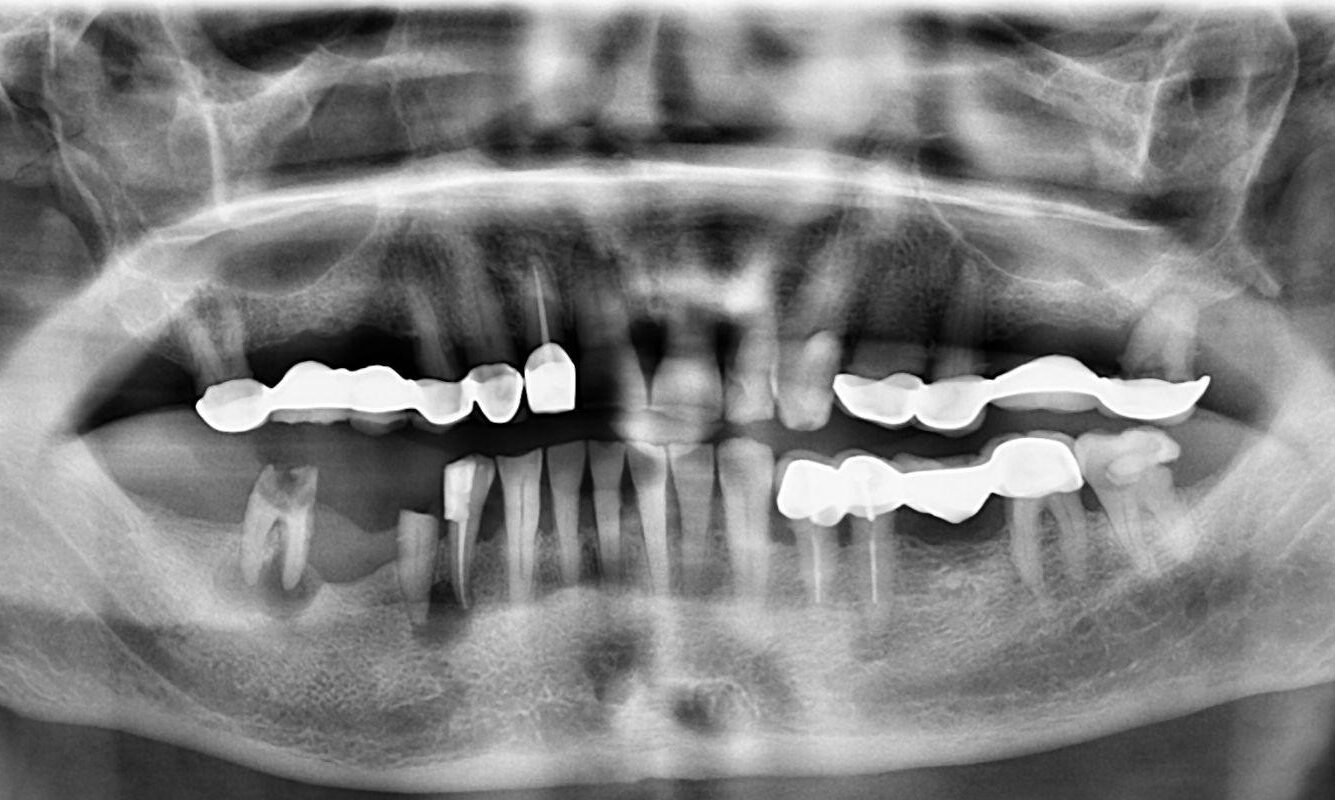

1.  What option cannot be selected for this panoramic X ray?

2 / 23